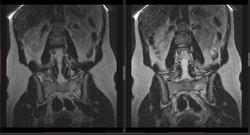

Женщина 1989 г.р. Жалуется на боли в крестце слева. С диагнозом грыжа L5-S1 направлена на МРТ ПОП, затем выполнена рентгенография крестца (это я делал, а не лаборанты, все тапки в меняwink). ДАЙКОМ

Думаю о "стресс" переломе, левой боковой массы крестца, а о чем думаете вы, уважаемые коллеги?

vadim losevichev wrote:

Это?

Видимо да, тут лучше видно

Almo wrote:

А, почему "стрессовый", а не банальный перелом?

Потому что линия не "сквозная" (не разделяет боковую массу на 2 части), нет травмы в анамнезе,а месяц назад начала интенсивно заниматься аэробикой.

Всё-таки не нужно стрессом все переломы теперь величать. Тем паче, что на 7 слайде есть линия, выходящая за кортикал. Перелом случается и не делит на части, а только трещиной ограничивается - кость целая, болит, но функционирует, а перелом в ней лежит и только на снимках себя проецирует.)